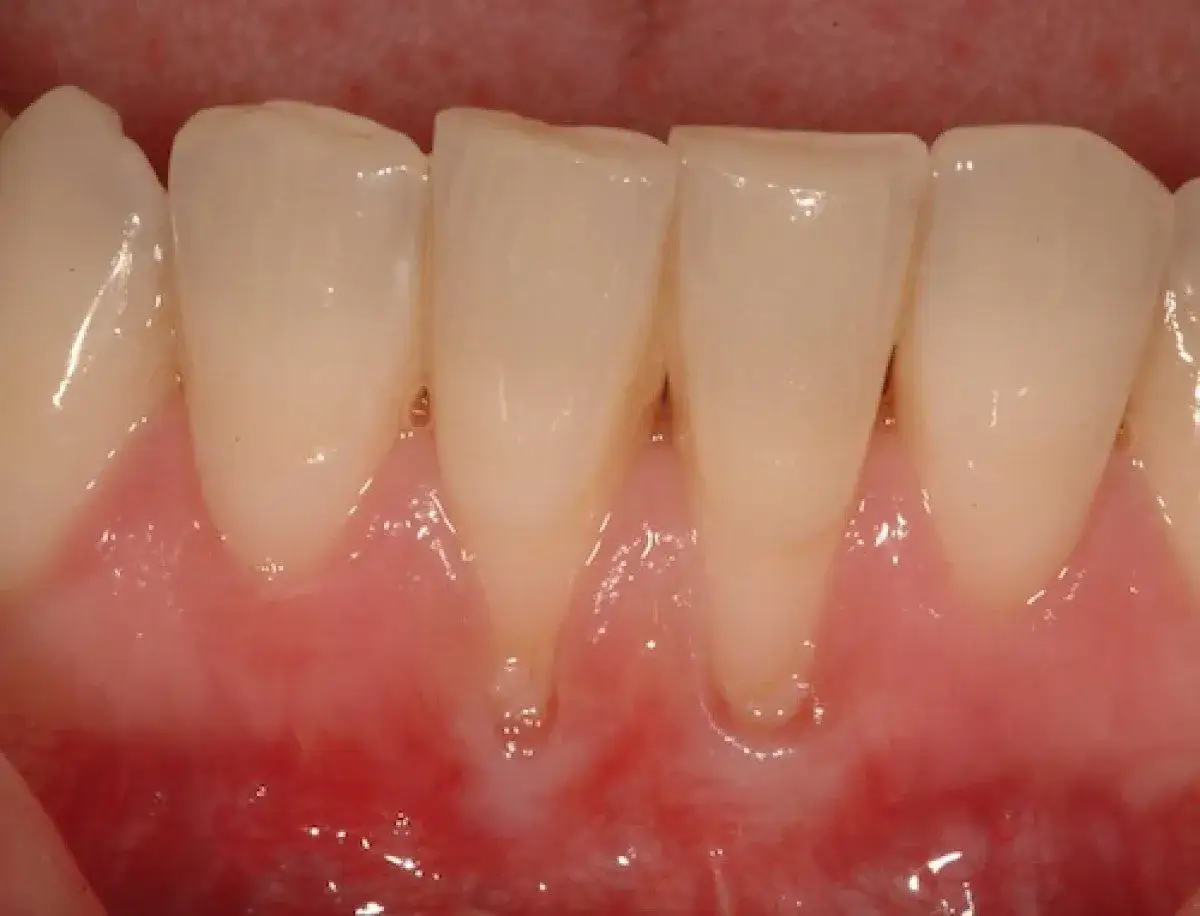

- „Wydłużenie” zębów: To jeden z najbardziej widocznych objawów. Zęby wydają się dłuższe niż kiedyś, ponieważ linia dziąseł cofa się, odsłaniając ich korzenie.

- Nadwrażliwość na zimno, słodkie lub dotyk: Odsłonięte korzenie zębów zawierają kanaliki z zakończeniami nerwowymi, które reagują na bodźce zewnętrzne. To właśnie nadwrażliwość jest często pierwszym i najbardziej dokuczliwym sygnałem alarmowym dla pacjentów.

- Zmiana koloru zęba: Odsłonięty korzeń ma zazwyczaj ciemniejszy, żółtawy odcień w porównaniu do korony zęba, co może wpływać na estetykę uśmiechu.

To jedno z najczęściej zadawanych pytań przez pacjentów. Odpowiedź jest niestety jednoznaczna: recesja dziąseł nie „odrasta” sama. Tkanka dziąsłowa, która uległa utracie, nie ma zdolności do naturalnej regeneracji w takim stopniu, aby pokryć odsłonięty korzeń. Oznacza to, że raz cofnięte dziąsło nie powróci samoistnie do swojej pierwotnej pozycji.